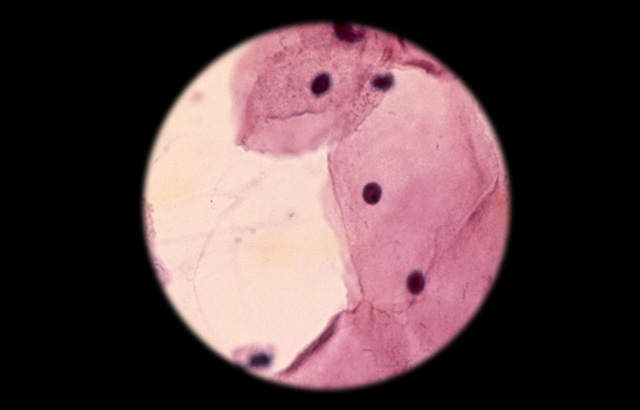

HPV is a virus that can cause cervical, vaginal, penile and anal cancers. More than 520,000 cases of cervical cancer are diagnosed worldwide each year (3,100 in the UK), causing around 266,000 deaths (800 in the UK). A common screening procedure for cervical cancer is the Pap smear, which tests for the presence of precancerous or cancerous cells on the cervix.